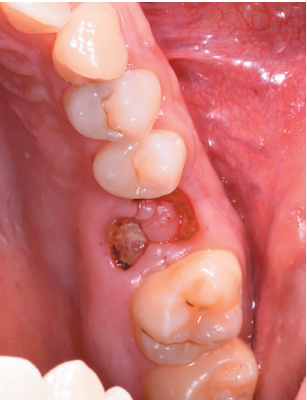

We present a clinical case of a 28-year-old male who presented severe pain in the second quadrant, associated with the presence of root remains located in the first left upper molar (2.6).

There were no medical-surgical antecedents of interest in his medical history, without known drug allergies or unhealthy habits. No relevant data was found on the extra oral examination. In the intraoral examination, non-restorable teeth were seen in the 2.6 and 4.6 position and the presence of retained lower third molars. (Figures 1 and 2).

The extraction of 4.6 and 2.6 and the curettage of the apical processes were planned, and the autotransplant of the left upper third molar (2.8) to sustain the 2.6 (Figure 5) was suggested to the patient.